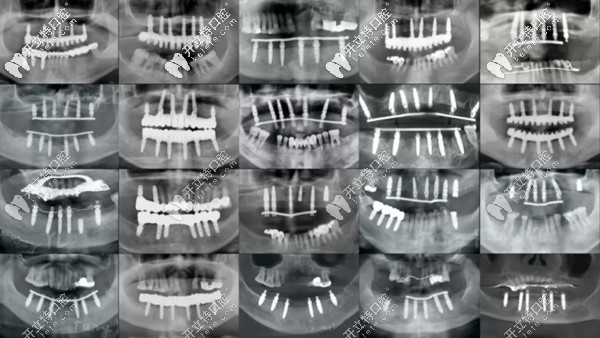

各類全口種植牙的全景片展示圖

(各類全口種植牙的全景片展示圖)

這么說吧,從上圖可以看出,即便同樣是全口種植牙,同樣是上下6顆種植體,同樣采用all-on-6即刻種植技術(shù),但用的植體長(zhǎng)短、粗細(xì)不等。

其實(shí)它們也代表了不同品牌、規(guī)格、型號(hào)的植體,所以,價(jià)位也是不能一概而論的。